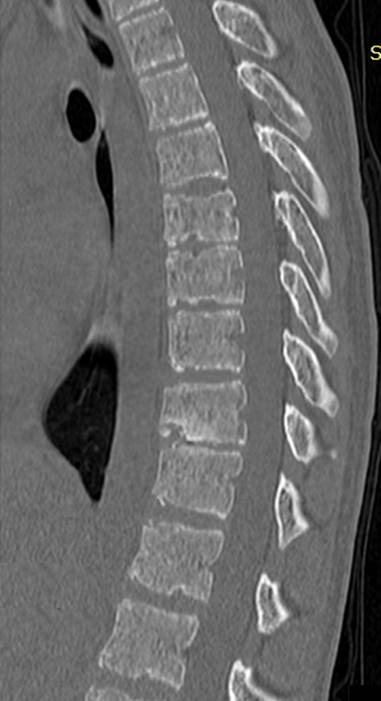

РК

– томография грудного отдела позвоночника того же ребенка, саггитальный скан,

который эквивалентен предыдущей рентгенограмме.

Хорошо видны хрящевые узлы различного размера, вдающиеся в тела

позвонков. Вокруг узлов заметно избыточное костеобразование – склероз

замыкательных пласитнок. Апофизарные кольца видны в виде точек повышенной

костной плотности у переднего и заднего краев тела позвонка, их изображение на

саггитальном скане не несет диагностической информации.

Аксиальный скан, виден крупный хрящевой узел в теле

позвонка (зеленая стрелка)